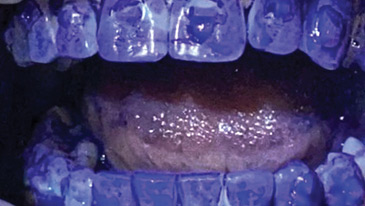

Enhanced Minimal Invasive Tooth Whitening

OH-Brostek-main alternate text for this image

Keywords Minimal Invasive Dentistry, Tooth whitening, White spot lesion, CPP-ACP, MI Paste Abstract This article discusses the philosophy behind the clinical protocols to achieve enhanced results in tooth whitening, and the successful reversal of enamel white spot lesions. External tooth whitening has long been recognized as having successful but variable results. An often-unintended consequence of … Read more